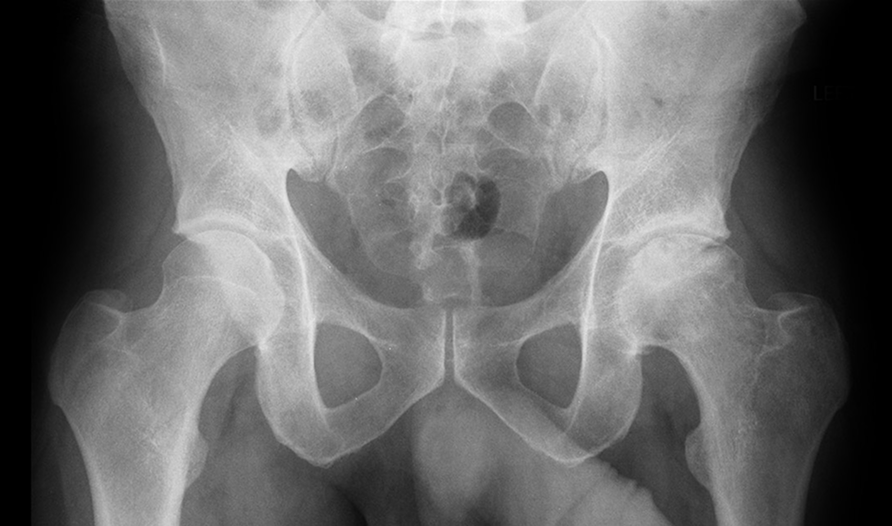

A study of RBhip was carried out in Denmark to assess the impact of using RBhip™ for Orthopaedic Surgeons and MSK Radiologists.

RBhip™ showed highest agreement with Orthopaedic expert staff

RBhip™ is able to identify key measurements needed for hip dysplasia diagnosis